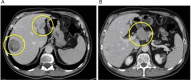

Hepatocellular carcinoma (HCC) is the most frequent primary hepatic cancer. Pathological features can define the biological behavior and prognosis. Medullary-like HCC is a very rare variant that has been described only twice in literature. In the present study, we report the case of a non-cirrhotic 72-year-old man, who presented two HCC lesions on routine screening for hepatitis C virus liver disease. Radiological imaging and biopsy showed two different subtypes: one classic HCC, which was treated with chemoembolization, and a second PET/CT-positive carcinoma with a PET/CT-positive metastatic coeliac lymph node, which was resected laparoscopically with a left lateral sectionectomy and extended lymphadenectomy. Histopathology revealed a medullary-like HCC; lymph node analysis confirmed the metastatic nature of the PET/CT-positive coeliac node and showed an incidental B-cell lymphoma in the hepatic pedicle lymph nodes. To the best of our knowledge this is the third case of medullary-like HCC described in the literature, and the first associated to a concomitant typical HCC.